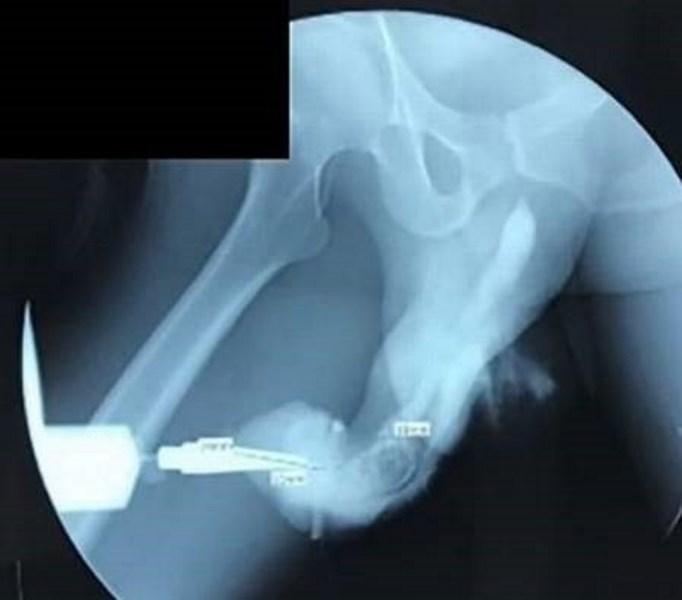

Homem de 50 anos sofre fratura no pênis durante ‘sexo mais vigoroso’Pênis fraturado após relação sexual 'mais vigorosa' na Indonésia – Foto: Reprodução/International Journal of Surgery Case Reports